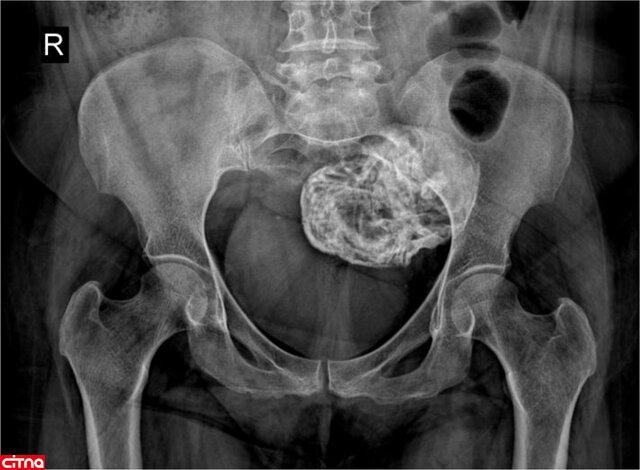

گزارش مورد نادر «جنین سنگی» در یک زن ۵۲ ساله ایرانی

در پی یافتن اتفاقی یک جنین سنگی در بدن یک زن ۵۲ ساله، گزارش این مورد نادر در یک مجله علمی بین‌المللی منتشر شد.

به گزارش ایسنا، «لیتوپدیون» یا جنین سنگی یکی از عوارض بسیار نادر حاملگی‌های خارج رحمی است که به صورت توده کلسیفیه در قسمتی از حفره شکم یا لگن ظاهر می‌شود. کلسیمی شدن یا کلسیفیکاسیون رسوب کلسیم در بافتی از بدن است.

در لیتوپدیون یا جنین سنگی، پس از لقاح، جنین خارج از رحم تشکیل می‌شود ولی به دلیل این‌که شرایط برای رشد آن مناسب نیست، پس از مدتی رشد متوقف می‌شود و شروع به کلسیمی شدن می‌کند. معمولاً فرد از وجود جنین سنگی در بدن خود مطلع نمی‌شود و سال‌ها بعد به صورت اتفاقی وجود آن مشخص می‌شود.

این یک پدیده نادر است که در ۱.۵ تا ۲ درصد از حاملگی‌های خارج از رحم ودر  ۰.۰۰۵۴ درصد از تمام حاملگی‌ها رخ می‌دهد.

اخیراً به صورت اتفاقی یک جنین سنگی از بدن یک زن ۵۲ ساله در ایران خارج شده و گزارش این اتفاق در مجله «Radiology Case Reports» منتشر شده است.

عضو گروه رادیولوژی بیمارستان شهید ستاری دانشگاه علوم پزشکی شهید بهشتی در مورد خارج کردن جنین سنگی از یک خانم ۵۲ ساله در ایران توضیح داد: در این مورد که اخیراً گزارش شده است، یک بیمار ۵۲ ساله به دنبال تصادف، به اورژانس مراجعه می‌کند. با یک عکس ساده لگن پزشکان متوجه وجود یک توده در بدن فرد می‌شوند و توده از طریق جراحی از بدن فرد خارج می‌شود. بر اساس بررسی‌های انجام‌شده، مشخص می‌شود که این توده «لیتوپدیون» یا جنین سنگی است.